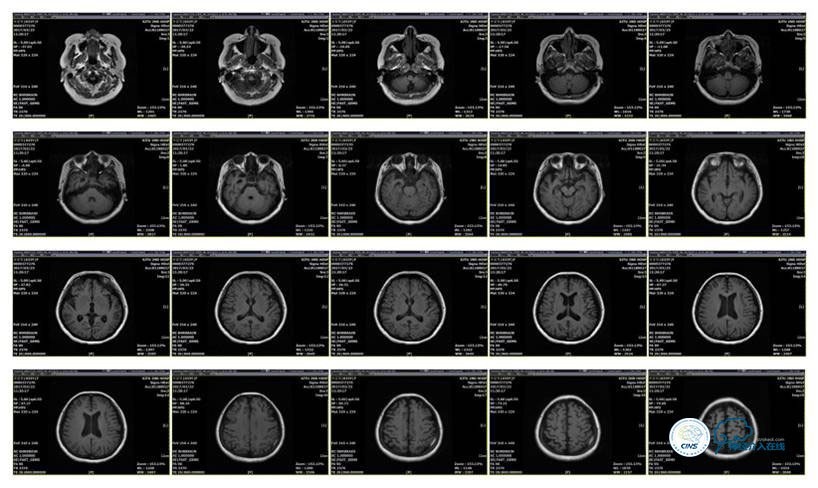

MRI T1

MRI T2

2016-5-19 MRI

2016-05-20 MRV

2016-06-03 CT

2017-06-07 CT